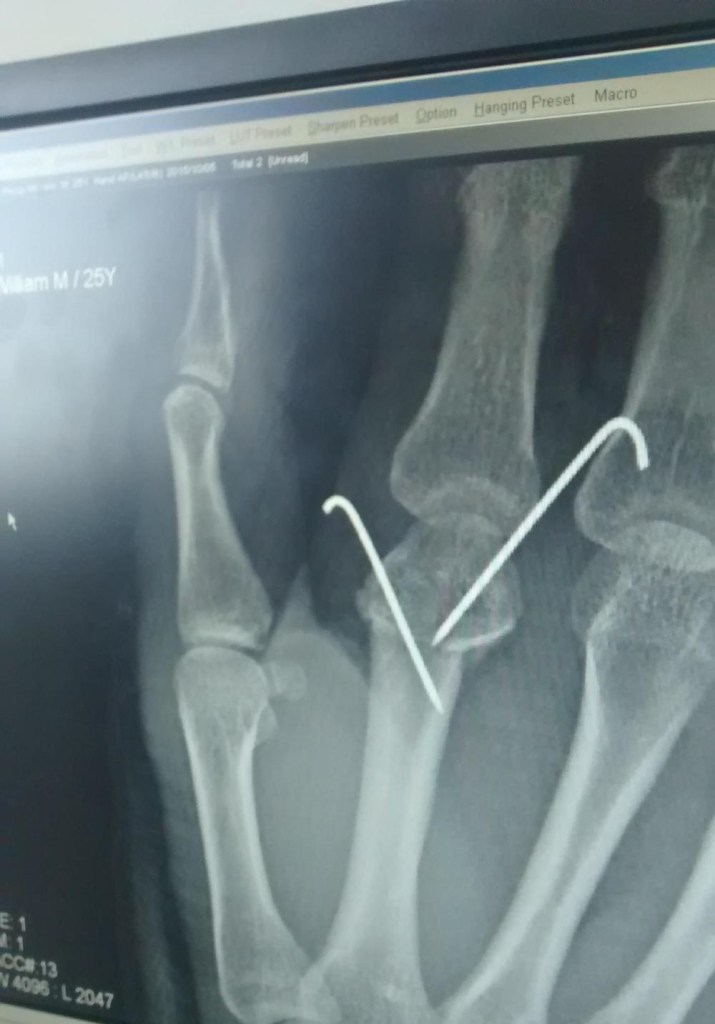

Flying over the dusty gravel tracks of the Mongolian steppe which I should have been pedallingIt was a pity to be robbed of the opportunity to cycle across this country, but I was safe and that’s all that matteredMy infected left hand finally stitched upA bandaged left hand…and a heavily bandaged right hand. My comical appearances meant I easily made friends at the hostel.Dan, one of the English trainee doctors analysing the x-ray of my fractured knuckleElana, the girl I had met in Istanbul, and stayed in contact with, had sent me this dramatic reinterpretation of the incidentEnjoying a proper drinking session, just what the doctor ordered! (Thanks to Simon for the photo)A parting shot post-surgery with Habu, the Mongolian TV host (Thanks to Habu for the photo)After such a great three weeks together, our group was finally splitting up. This was Dan and Rosie’s farewell dinner.Which was swiftly followed by Dom and Tobias’ farewell drinks. Here Markus, me and Tobias enjoy some Oktoberfest drinksWhen my bandages were being replaced by Zolboo and Baljka, I was able to catch a glimpse of the metal pins awkwardly sticking out of my handAn x-ray of the same pins showing how far they were embedded into my handDelighted to be reunited with Kim in Bishkek. Here we enjoy some of his great Korean cooking.To offset the grim photos of my hands, have some photos of Kim’s kitten, PyoPyo liked to watch Brooklyn Nine-Nine with meAnd would get annoyed when I started typing on my laptop, sitting on my hand to stop me